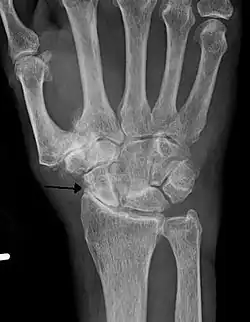

X-ray of erosive osteoarthritis of the fingers, also zooming in on two joints with the typical "gull-wing" appearance

Both primary generalized nodal osteoarthritis and erosive osteoarthritis (EOA, also called inflammatory osteoarthritis) are subsets of primary osteoarthritis. EOA is a much less common and more aggressive inflammatory form of osteoarthritis, which often affects the distal interphalangeal joints of the hand and has characteristic articular erosive changes on X-ray.[60]